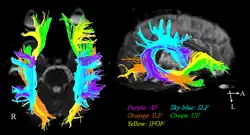

As the corpus callosum is substantially smaller in surface area relative to the longitudinal fissure (Figure 3), fiber bundles passing through are densely packed together, and precision tracking is essential to distinguish between the individual bundles that originate from and lead to the same cortical centers. Understanding such connections allows us to understand the contralateral concurrences and what diseases can result from lesions to them. Diffusion tensor imaging (DTI or dMRI) along with fiber-tracking (FT) algorithms and functional Magnetic Resonance Imaging (fMRI) is used to image these bundles.[26][27] For instance, occipital-callosal fiber tracts were localized with 1–2 mm precision using DTI-TF techniques - which are very important for the cooperation of visual cortices, and any lesion to them can lead to alexia, the inability to read.